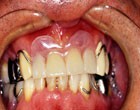

「牽引感が少しあったが、ほとんど何も感じなかった」とのこと。

作っておいた仮歯を装着。

全く痛みなし。

無麻酔のツボを刺激しただけの抜歯だと傷の治りの早いのがわかる。